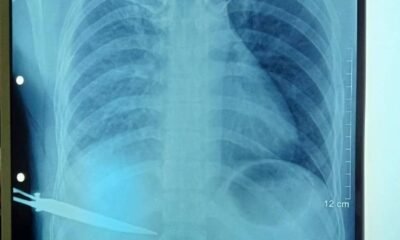

Hatutan.com, (09 Janeiru 2023), Díli—Kazu insidente sona kanek vítima iha área Bidau, besik Ponte BJ Habibie iha Sábadu (07/01/2023), to’o oras-ne’e seidauk bele fó ninia deklarasaun...